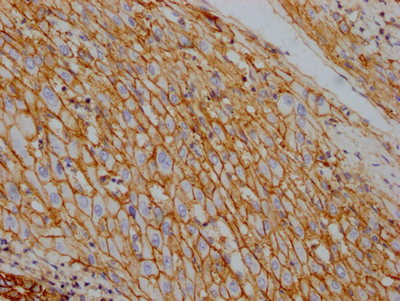

IHC image of CSB-RA796310A0HU diluted at 1:100 and staining in paraffin-embedded human liver cancer performed on a Leica BondTM system. After dewaxing and hydration, antigen retrieval was mediated by high pressure in a citrate buffer (pH 6.0). Section was blocked with 10% normal goat serum 30min at RT. Then primary antibody (1% BSA) was incubated at 4℃ overnight. The primary is detected by a Goat anti-rabbit IgG polymer labeled by HRP and visualized using 0.05% DAB.

IHC image of CSB-RA796310A0HU diluted at 1:100 and staining in paraffin-embedded human kidney tissue performed on a Leica BondTM system. After dewaxing and hydration, antigen retrieval was mediated by high pressure in a citrate buffer (pH 6.0). Section was blocked with 10% normal goat serum 30min at RT. Then primary antibody (1% BSA) was incubated at 4℃ overnight. The primary is detected by a Goat anti-rabbit IgG polymer labeled by HRP and visualized using 0.05% DAB.